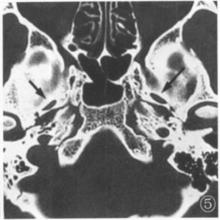

圖2 卵圓孔為長條形該組CT測得國人卵圓孔的長徑均值為8.04mm、寬徑均值為4.05mm。與陳盛剛 觀測的長徑7.2mm,寬徑3.5mm和曹煥軍 測量的長徑7.55mm,寬徑3.97mm,與何玉泉 測量的長徑7.54mm、寬徑均值為3.66mm基本相符。本組長徑與寬徑之比約為2:1。長徑、寬徑均值在男女各組都是左側略大於右側。在側別上,男女左右長徑均值無顯著性差異(P>0.05),而左右寬徑有顯著性意義(P<0.05)。從而推測國人卵圓孔面積左側均稍大於右側。這反映了國人卵圓孔周圍骨質在個體發育時的不對稱性,是否與神經中,第Ⅴ對腦神經—三叉神經發育時的不對稱性有關。也可能與優勢半球有關。需作進一步研究。也可能與長條形卵圓孔有關。